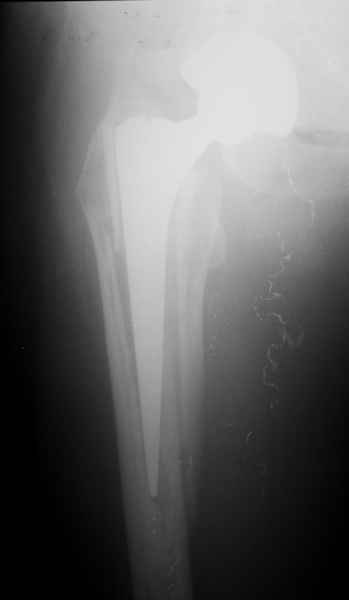

Произведено закрытое удлинение ножки эндопротеза с помощью ретроградного интрамедуллярного стержня. Продолжительность операции 3 часа. Два из них закрытое восстановление длины бедра диистрактором

таз-бедро.

А нельзя ли увидеть и профиль бедра на всем протяжении, т.е. и весь протез, и весь стержень? И фас бы с коленом.

новые снимки

Пациента удалось осмотреть недавно. Достигнутый результат сохраняется. Перелом бедра сросся. Конечность опорная и безболезненная, ходит без трости. Ножка, похоже, реинтегрировалась, как и надеялись. Снимки и фото в приложении. Комментарии приветствуются.

Надо ли что-то делать дальше, как полагаете? Убрать винты? Убрать "удлинитель ножки"? Или оставить все, как есть? Спасибо заранее.